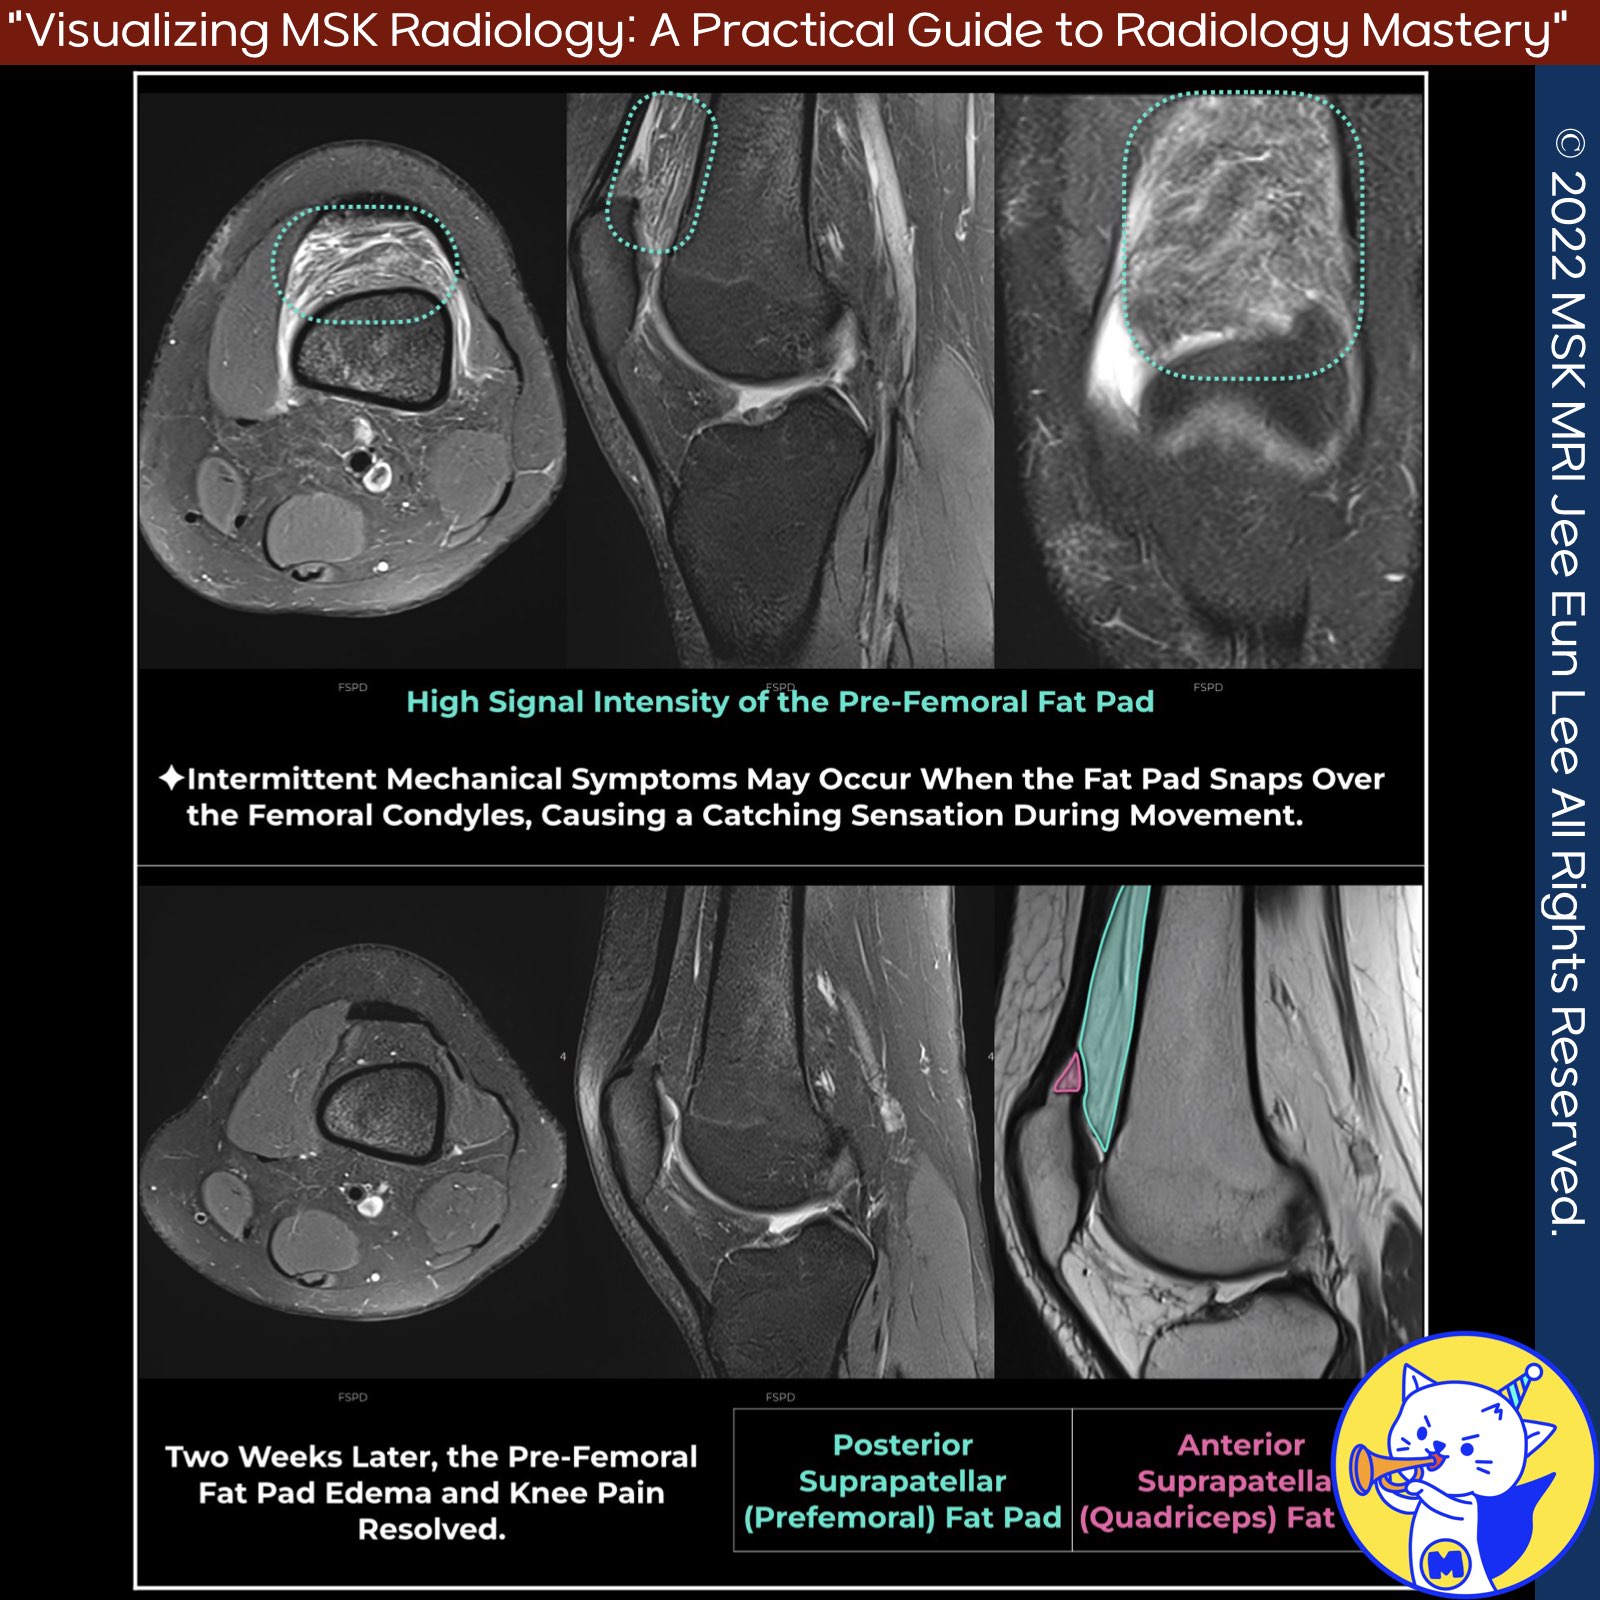

📌 Posterior Suprapatellar (Prefemoral) Fat Pad

- The posterior suprapatellar (prefemoral) fat pad can be a source of chronic anterior knee pain, particularly proximal to the superior pole of the patella.

- This condition may cause intermittent mechanical symptoms, such as a catching sensation during motion, when the fat pad snaps over the femoral condyles.

- Chronic impingement of the prefemoral fat pad can lead to nonencapsulated fibrosis, which can result in intermittent catching sensations during movement .

- However, the association between pre-femoral fat pad edema and anterior knee pain is controversial, as it can also be an asymptomatic finding in high-level athletes .